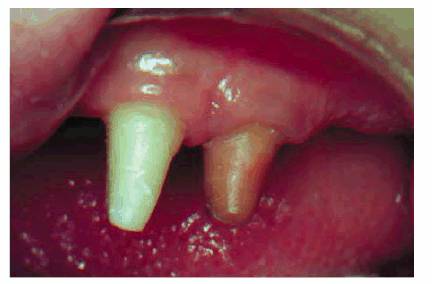

If the remaining tooth structure is insufficient to adequately retain a

restoration, the need for endodontics should be considered. Although an

argument may exist to support the use of pin-retained restorations, the degree

of injury of pin placement and the risk of fracture predispose elective

endodontics and a full crown. The only exception would be a tooth with

incomplete root apex formation. Once the root canal therapy is completed, a

post and core can be fabricated to provide the ideal restorative condition.

However, when the pulp is exposed, endodontic intervention is indicated (Figure 19-57): either complete root canal

therapy when the root is fully formed or an apexification procedure in a tooth

with an open apex.2 Innovative solutions are required to provide for